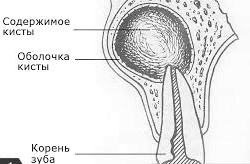

Кіста - слово, яке з давньогрецької перекладається як міхур, що ідеально описує захворювання. Це порожнину, що формується в органах і тканинах, відмежована від здорової тканини щільною оболонкою, яка, до того ж, має внутрішній вміст. Симптоми захворювання можуть бути найрізноманітніші.

Вміст кістозної порожнини може бути найрізноманітнішим. На самому початку захворювання вона може бути порожнистої або заповнена рідиною, характерною для органу, в якому вона утворюється. Однак клітини внутрішньої вистилки стінок продукують серозний секрет, якого згодом стає все більше і більше, відтоку немає, тому розтягується сама порожнину, стаючи все більше і приносячи дискомфорт і порушення функції. Але навіть стаючи великих розмірів, вони не завдають особливої шкоди здоров'ю, тільки якщо не передавлюють життєво важливі органи. Виражена клінічна картина буде спостерігатися, якщо патологічний процес нагноится за рахунок приєднання гноеродной мікрофлори у внутрішній ексудат.